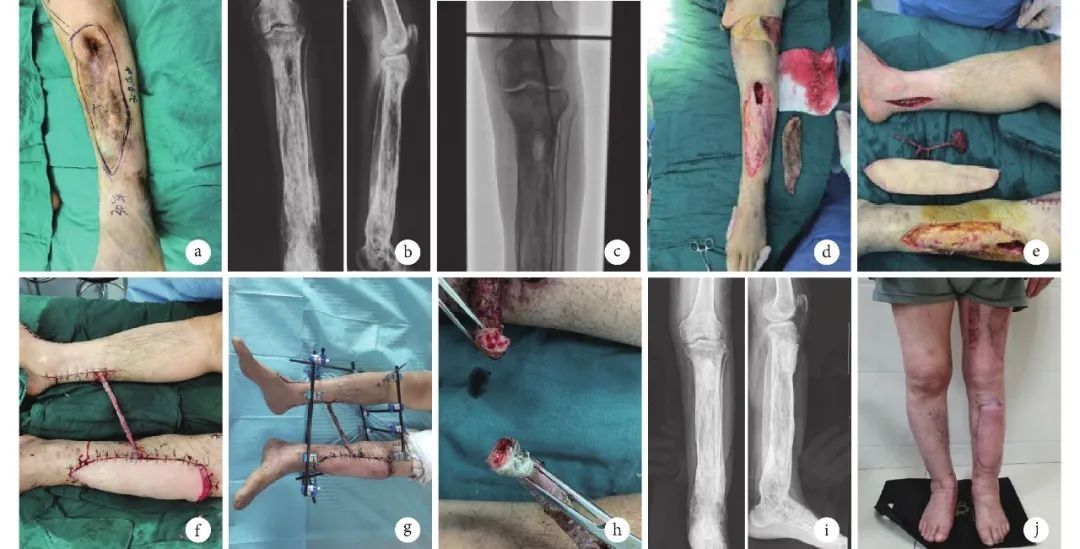

图 2 典型病例2 a. 术前外观;b. 术前正侧位X 线片;c. 术前血管造影;d. 术中彻底清创后创面;e. 术中股前外侧肌皮瓣切取;f.桥式皮瓣修复创面及游离植皮包裹血管桥;g. 术后4周皮瓣及血管桥;h. 断蒂血管桥的断端;i.术后6个月正侧位X线片;j. 术后6个月皮瓣及供区外观

本组男9 例,女2 例;年龄11~60 岁,中位年龄39 岁。左侧5例,右侧6例。交通事故伤致小腿软组织缺损8例,受伤至入院时间1 h~2个月,中位时间12 d;慢性骨髓炎致小腿皮肤大面积感染3例,病程分别为2、5、30 年。清创后皮肤软组织缺损范围为10 cm×8 cm~35 cm×10 cm;均伴骨、肌腱外露。9 例小腿仅存1条主干血管,2 例受区无法找到可与皮瓣血管吻合的血管。7例合并胫腓骨骨折。

结果 术后患者皮瓣均完全成活,无皮瓣坏死、感染及动静脉危象发生。患者血管桥血供通畅,搏动良好,表面回植的中厚皮片色泽红润。11例患者均获随访,随访时间2~40个月,平均19.4个月。皮瓣与周围组织愈合良好,无明显渗出,色差小;皮瓣色泽及温度正常、血运良好、质地柔软,皮瓣外形及小腿轮廓均满意,且患肢功能恢复良好。大腿皮瓣供区创面Ⅰ期愈合,无明显瘢痕形成;皮片供区愈合良好,可见纵向长方形瘢痕,外观满意。